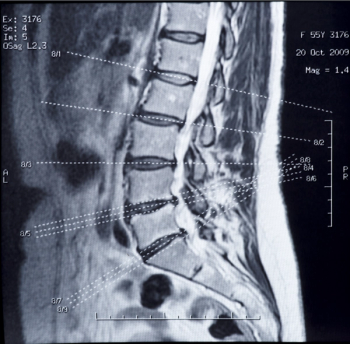

Low back pain is one of the most common reasons patients seek primary care; 3 new studies confirm what most of them don’t want to hear: less treatment is better than more.

Steroid injections for low back pain, tennis elbow, provide acute relief, but perhaps long-term damage.

Epidural steroid injections turned deadly raise pointed controversy over poor oversight of compounding pharmacies. But tainted or not, are the injections a valid therapy for back pain at all? Here, one expert’s opinion.